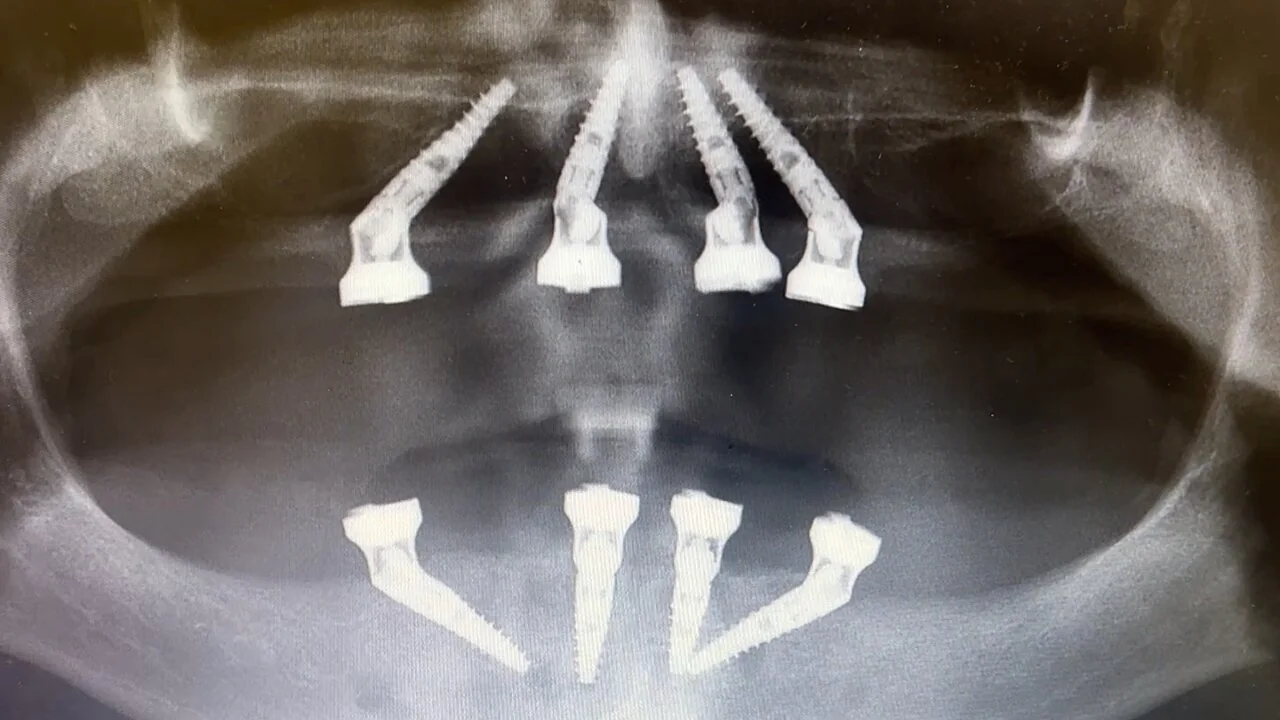

Siden Mikkel hadde lite kjeveben, ble behandlingen gjort etter prinsippet bak All on 4 – der implantat settes på skrå for å utnytte tilgjengelig ben.

- Implantater i begge kjever